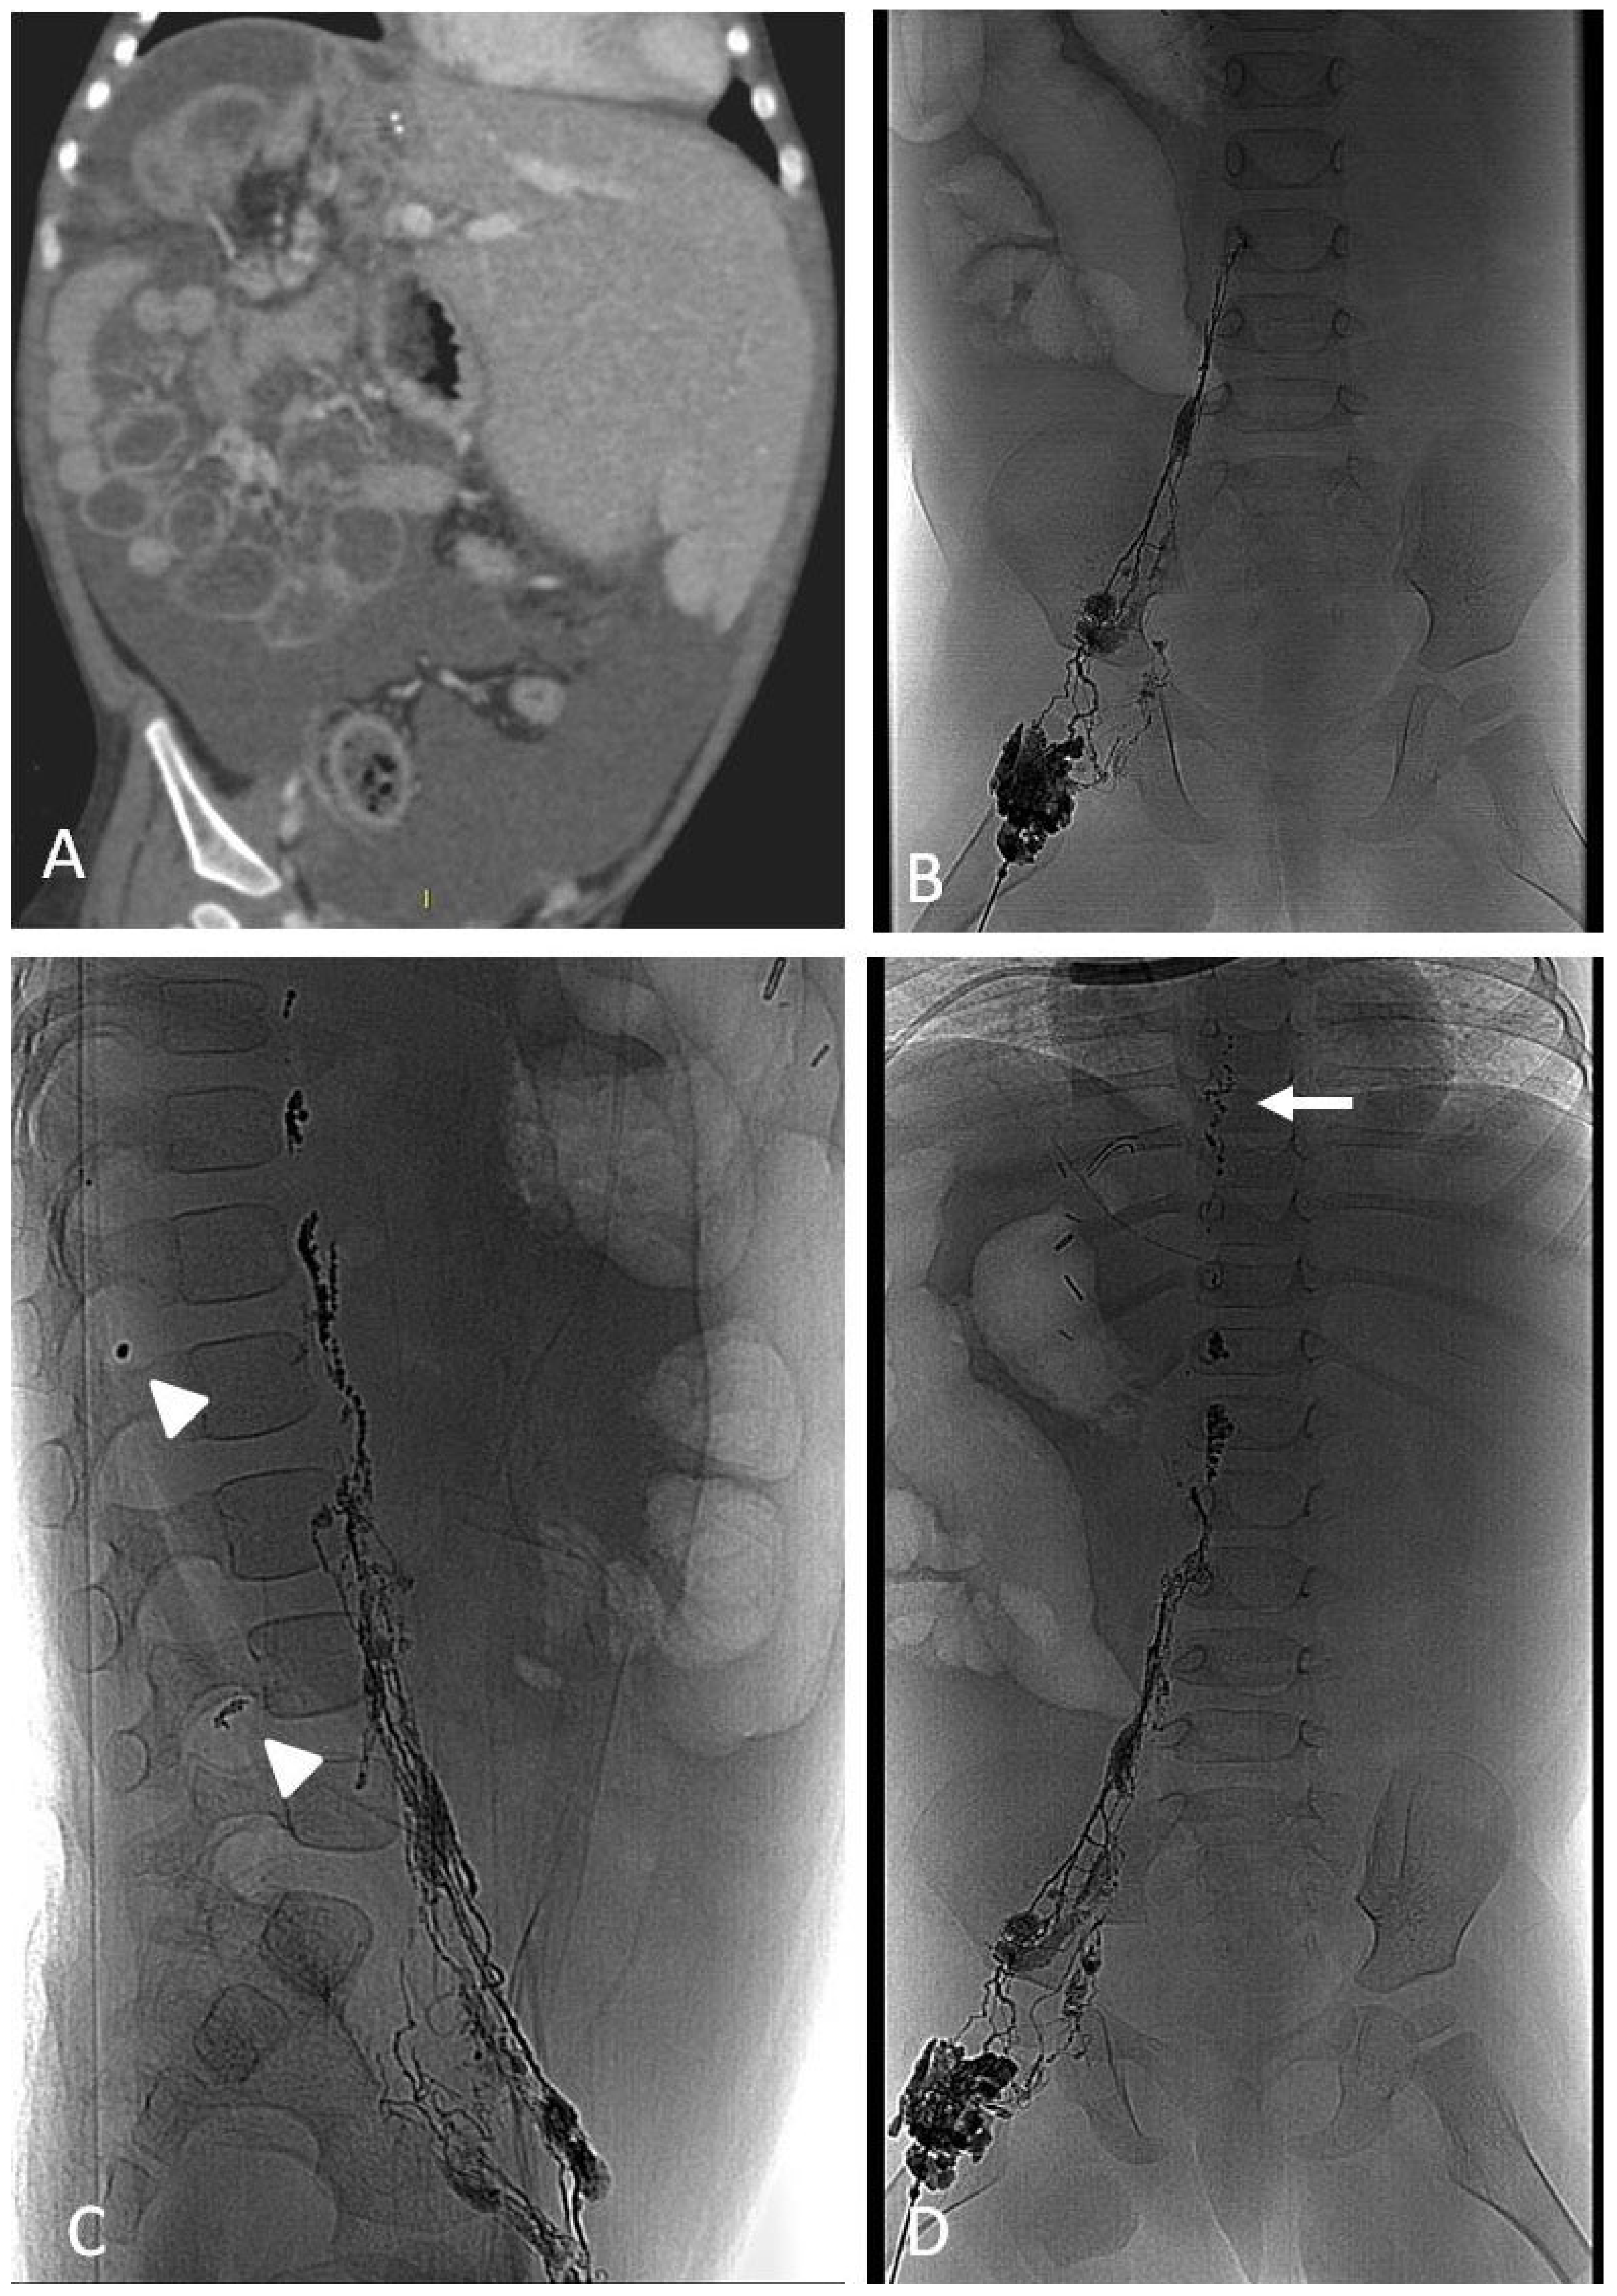

11. Lymphatic Embolization

11.2. Lymphatic Leakages, Chylothorax and Chylous Ascites

11.2.1. Techniques

11.2.2. Clinical Outcomes